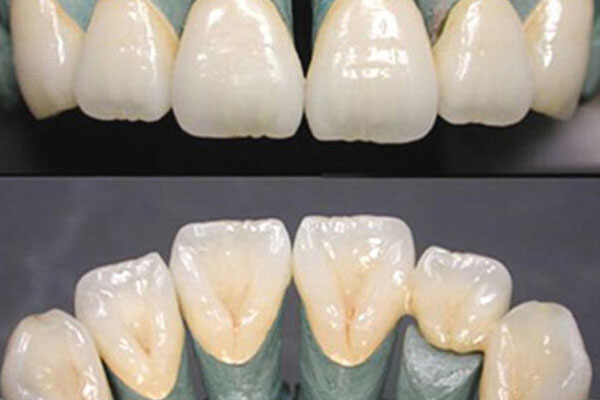

牙齿缺失不仅会影响咀嚼功能,还可能导致邻近牙齿倾斜、对颌牙齿伸长,从而引发牙齿疼痛。如果你有牙齿缺失的情况,中老年口腔的种植牙和活动义齿修复方案能够快速恢复你的牙齿功能,避免因牙齿缺失引发的疼痛问题。我们的修复技术不仅高效,还能让你的牙齿看起来更加自然。